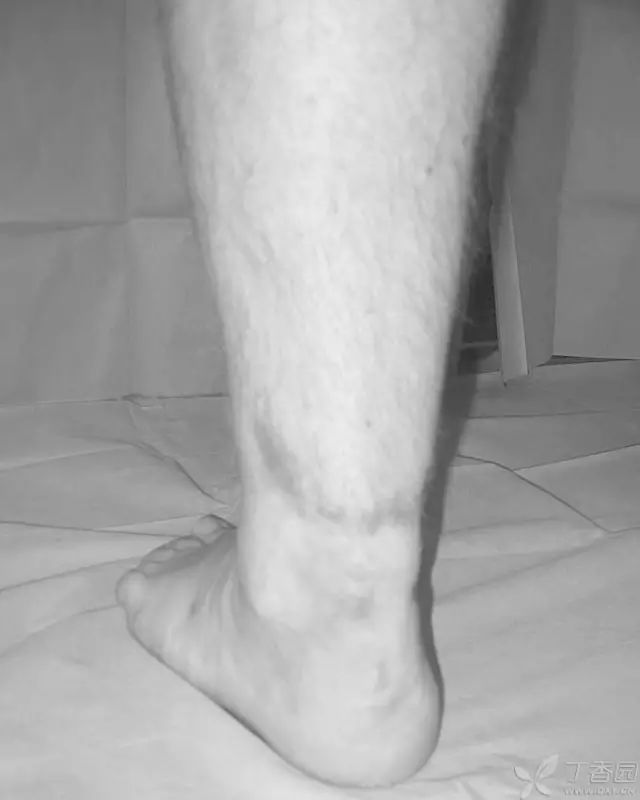

33 岁男性,车祸多发伤。左踝严重污染,几乎环形创口,胫骨远端 20 cm 缺损

游离骨块生理盐水灌洗,保持湿润,4 小时内紧急手术。术中对创口和游离骨块各用 12L 生理盐水灌洗,彻底清创。外固定支架固定,创口松散地缝合

原计划 48 小时再次灌洗,因身体情况不稳定,10 天后再次进手术室清创灌洗,方法如前;48 小时后进行了第三次灌洗,然后进行了内固定,闭合创口。

3 个月后创口无感染迹象,骨折处无压痛

6 个月后,骨折线模糊,独立行走

18 个月恢复工作